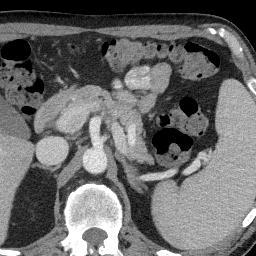

Finally, Fig. 9 displays examples of output probability maps from all of the comparative methods, i.e., HNN [12], UNet [16], PNet-MSA and “PNet-MSA+BiRNN”, where the latter one delivers the sharpest and clearest output on both CT and MRI datasets. More specifically, PNet-MSA presents results that are detailed and recover the major part of the pancreas, where both HNN and UNet suffer from significant low segmentation recall. When observing the BiRNN outputs for CT and MRI, we find detailed pancreas parts in CT have been recovered via shape continuity learning and regularization, while in MRI, the BiRNN only outputs probability map with the same shape in PNet-MSA’s output, which is optimal when the inter-slice shape changes drastically in the MRI dataset. Thus, BiRNN would help to refine pancreas segmentation with a smoothed surface in the situation that slice thickness of the 3D scans is reasonably small, e.g., <2absent2<2mm.

Refer to caption

(a)

(b)

(c)

(d)

(e)

(f)

(g)

(h)

(i)

(j)

(k)

(l)

(m)

(n)

(o)

(p)

(q)

(r)

(s)

(t)

(u)

(v)

(w)

(x)

Figure 9: Examples of output probability map: columns from left to right are the input CT/MRI image, results from HNN [12], UNET [16], the proposed PNet-MSA sub-network, and the full CNN-RNN (“PNet-MSA+BiRNN”), and the ground truth. Our model delivers the most clear probability maps which preserve detailed pancreatic boundaries.